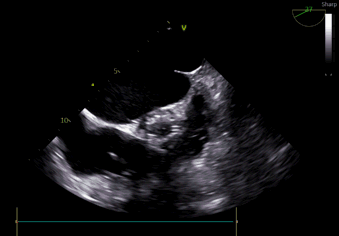

3. 全程无造影剂超声引导下行TAVI手术对超声团队高精度和快速判断要求极高,了解手术过程并同频配合术者手术操作,同时要求术者对超声解读深刻。

术中导丝跨瓣后20mm球囊预扩,超声判断冠脉风险尚可,植入L23 VenusA Plus可回收瓣膜位置良好,用23mm球囊后扩支架下缘,微少量瓣周漏。

术后即刻血压135/65mmHg,狭窄解除,释放后超声测量瓣下支架长度6mm标准位释放瓣膜位置完美。整台手术用时不足1.5小时,麻醉、超声等团队全程协作为手术顺利完成保驾护航。